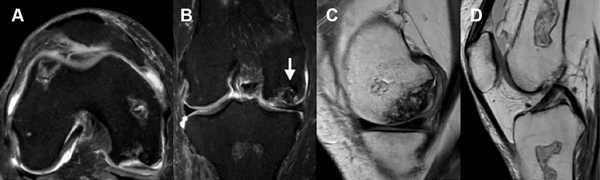

La resonancia magnética (RM) de la rodilla derecha evidenciaba imágenes compatibles con infartos óseos en metáfisis femoral, metáfisis tibial, tróclea femoral externa y meseta tibial homolateral que corresponde a un estadio II de la clasificación de Ficat y Arlet (fig. 2). En la RM de la rodilla izquierda se observaban múltiples infartos óseos en ambas mesetas tibiales, metáfisis tibial y metáfisis femoral, junto a foco de osteonecrosis en cara inferior del cóndilo femoral interno (fig. 3) que corresponde a un estadio III de la clasificación de Ficat y Arlet.

Figura 2: Resonancia magnética de rodilla derecha. A) Corte axial. B) Corte coronal. C y D) Cortes sagitales con focos osteonecróticos en ambos cóndilos femorales y en metáfisis femoral y tibial.

Figura 3: RM de rodilla izquierda. A) Corte axial. B) Corte coronal. C y D) Cortes sagitales. Múltiples infartos óseos difusos. Pequeño foco de osteonecrosis en la cara inferior del cóndilo femoral interno. Mayor afectación en mesetas y metáfisis tibial.